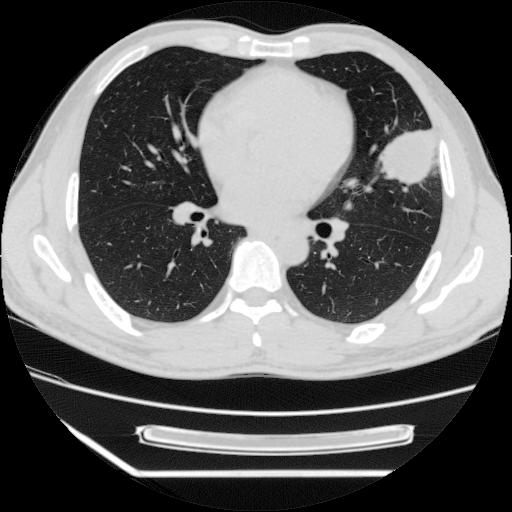

男,38岁,于2009年8月9日晚突发左侧胸痛,今x线提示左下肺阴影,为了明显确诊断,行ct检查,

血常规:嗜酸性细胞增高,单核细胞增高。

病灶发生在下叶,密度均匀,边缘模糊、毛糙,周围血管纹理增强扭曲改变,靠近胸膜处病灶胸膜反应明显。

支持考虑---球形肺炎。

左肺舌叶病变。主体病灶呈类圆形中心密度低,成液化趋势周边班片影分布

考虑肺脓肿

虽然实验室检查支持炎性病变,且病变内有坏死改变(中央呈大片状低密度影),但仍不能掉以轻心,鳞癌也可以有这种影像改变。